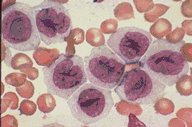

ANLL-M-5B

ANLL M5B: The monocytoid cells in this peripheral blood smear, at

low oil magnification, show much more mature monocytic nuclei.